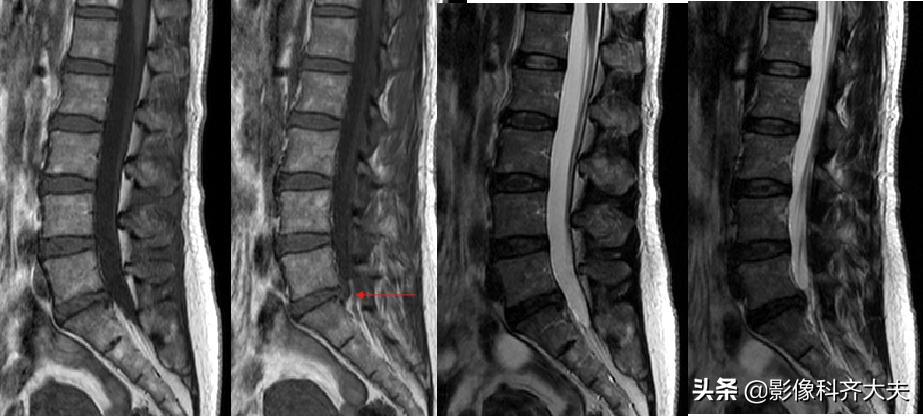

MRI:椎间盘突出(外侧型)

MRI:腰椎间盘右后突出

MRI:腰4、5间盘变性、突出,硬膜囊受压

MRI:腰椎间盘突出

MRI:腰 5-骶1间盘脱出

MRI:腰椎间盘脱出

MRI:髓核游离